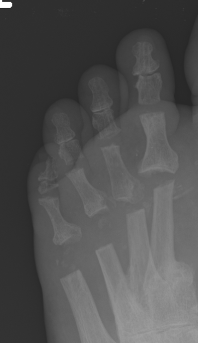

3. Altered forefoot biomechanics / Transfer metatarsalgia

| Hyper-extended MTPJ | Short 1st MT | 1st ray insufficiency syndrome | Iatrogenic |

|---|---|---|---|

| Claw toe / hammer toe | > 2 cm back from 2nd MT |

Splayed forefoot |

Bunion surgery |

| Cavus foot | 1st ray unloaded | 1st ray unloaded | MT head excision |